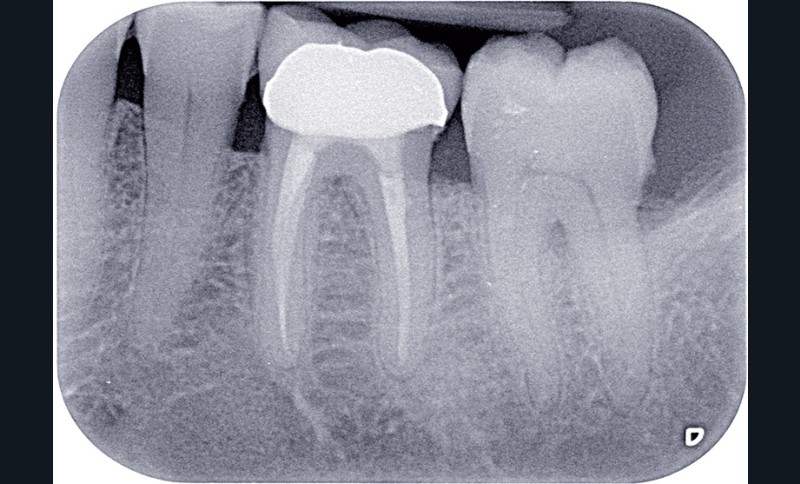

La dentisterie contemporaine privilégie les modes de restauration conservateurs avec pour objectif de préserver la vitalité pulpaire. Cependant, des échecs peuvent survenir du fait de nouvelles agressions et ce, malgré la qualité des procédures opératoires mises en œuvre (fig. 1).

Dans ces situations, le praticien est conduit à dépulper et à restaurer les dents traitées endodontiquement. Les traitements doivent alors s’inscrire dans le concept du continuum endo-restaurateur qui a été défini comme étant « le processus spatio-temporel sans interruption ni rupture qui débute par l’accès à l’endodonte et s’achève avec la mise en place de la restauration prothétique d’usage » (1). Il existe bien une continuité, du traitement endodontique à la restauration fonctionnelle d’usage qui conditionne le pronostic et les résultats du traitement à long terme (fig. 2).